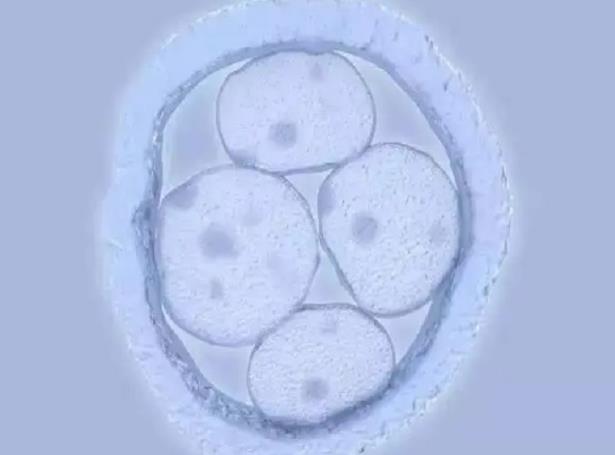

为什么国内的三代试管医生都建议优先移植新鲜胚胎?

为什么国内的三代试管医生都建议优先移植新鲜胚胎?我在准备三代试管婴儿。我进了一个交流群,发现里面的三代姐妹很多都是医生,建议优先移植新鲜胚胎。但是我记得冷冻胚胎..

剖析试管是移植新鲜卵好还是冻卵,对比成功率就一目了然

冻卵就是使用冷冻技术将卵子放在零下196摄氏度的液氮中进行保存,能够帮助女性保存生育能力。但是由于冻卵会受到取卵、保存、冷冻和后期解冻复苏等多方面的影响,因此和新..